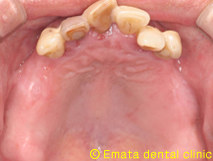

治療前